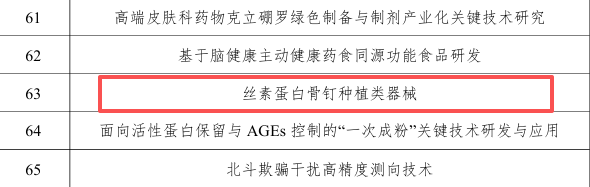

依托技术创新与产业协同,易天然医疗持续巩固领先优势。公司深度契合国家药监局 “春雨行动”临床创新成果转化导向,以源头创新、医工协同为核心,借助政策技术指导与审评支持,进一步优化研发路径、加速成果落地。同时,凭借长沙市揭榜挂帅项目、湖南省科技厅重大研发项目。双重政府背书,获得资金与政策双重扶持,为三类器械研发与转化提供坚实保障。